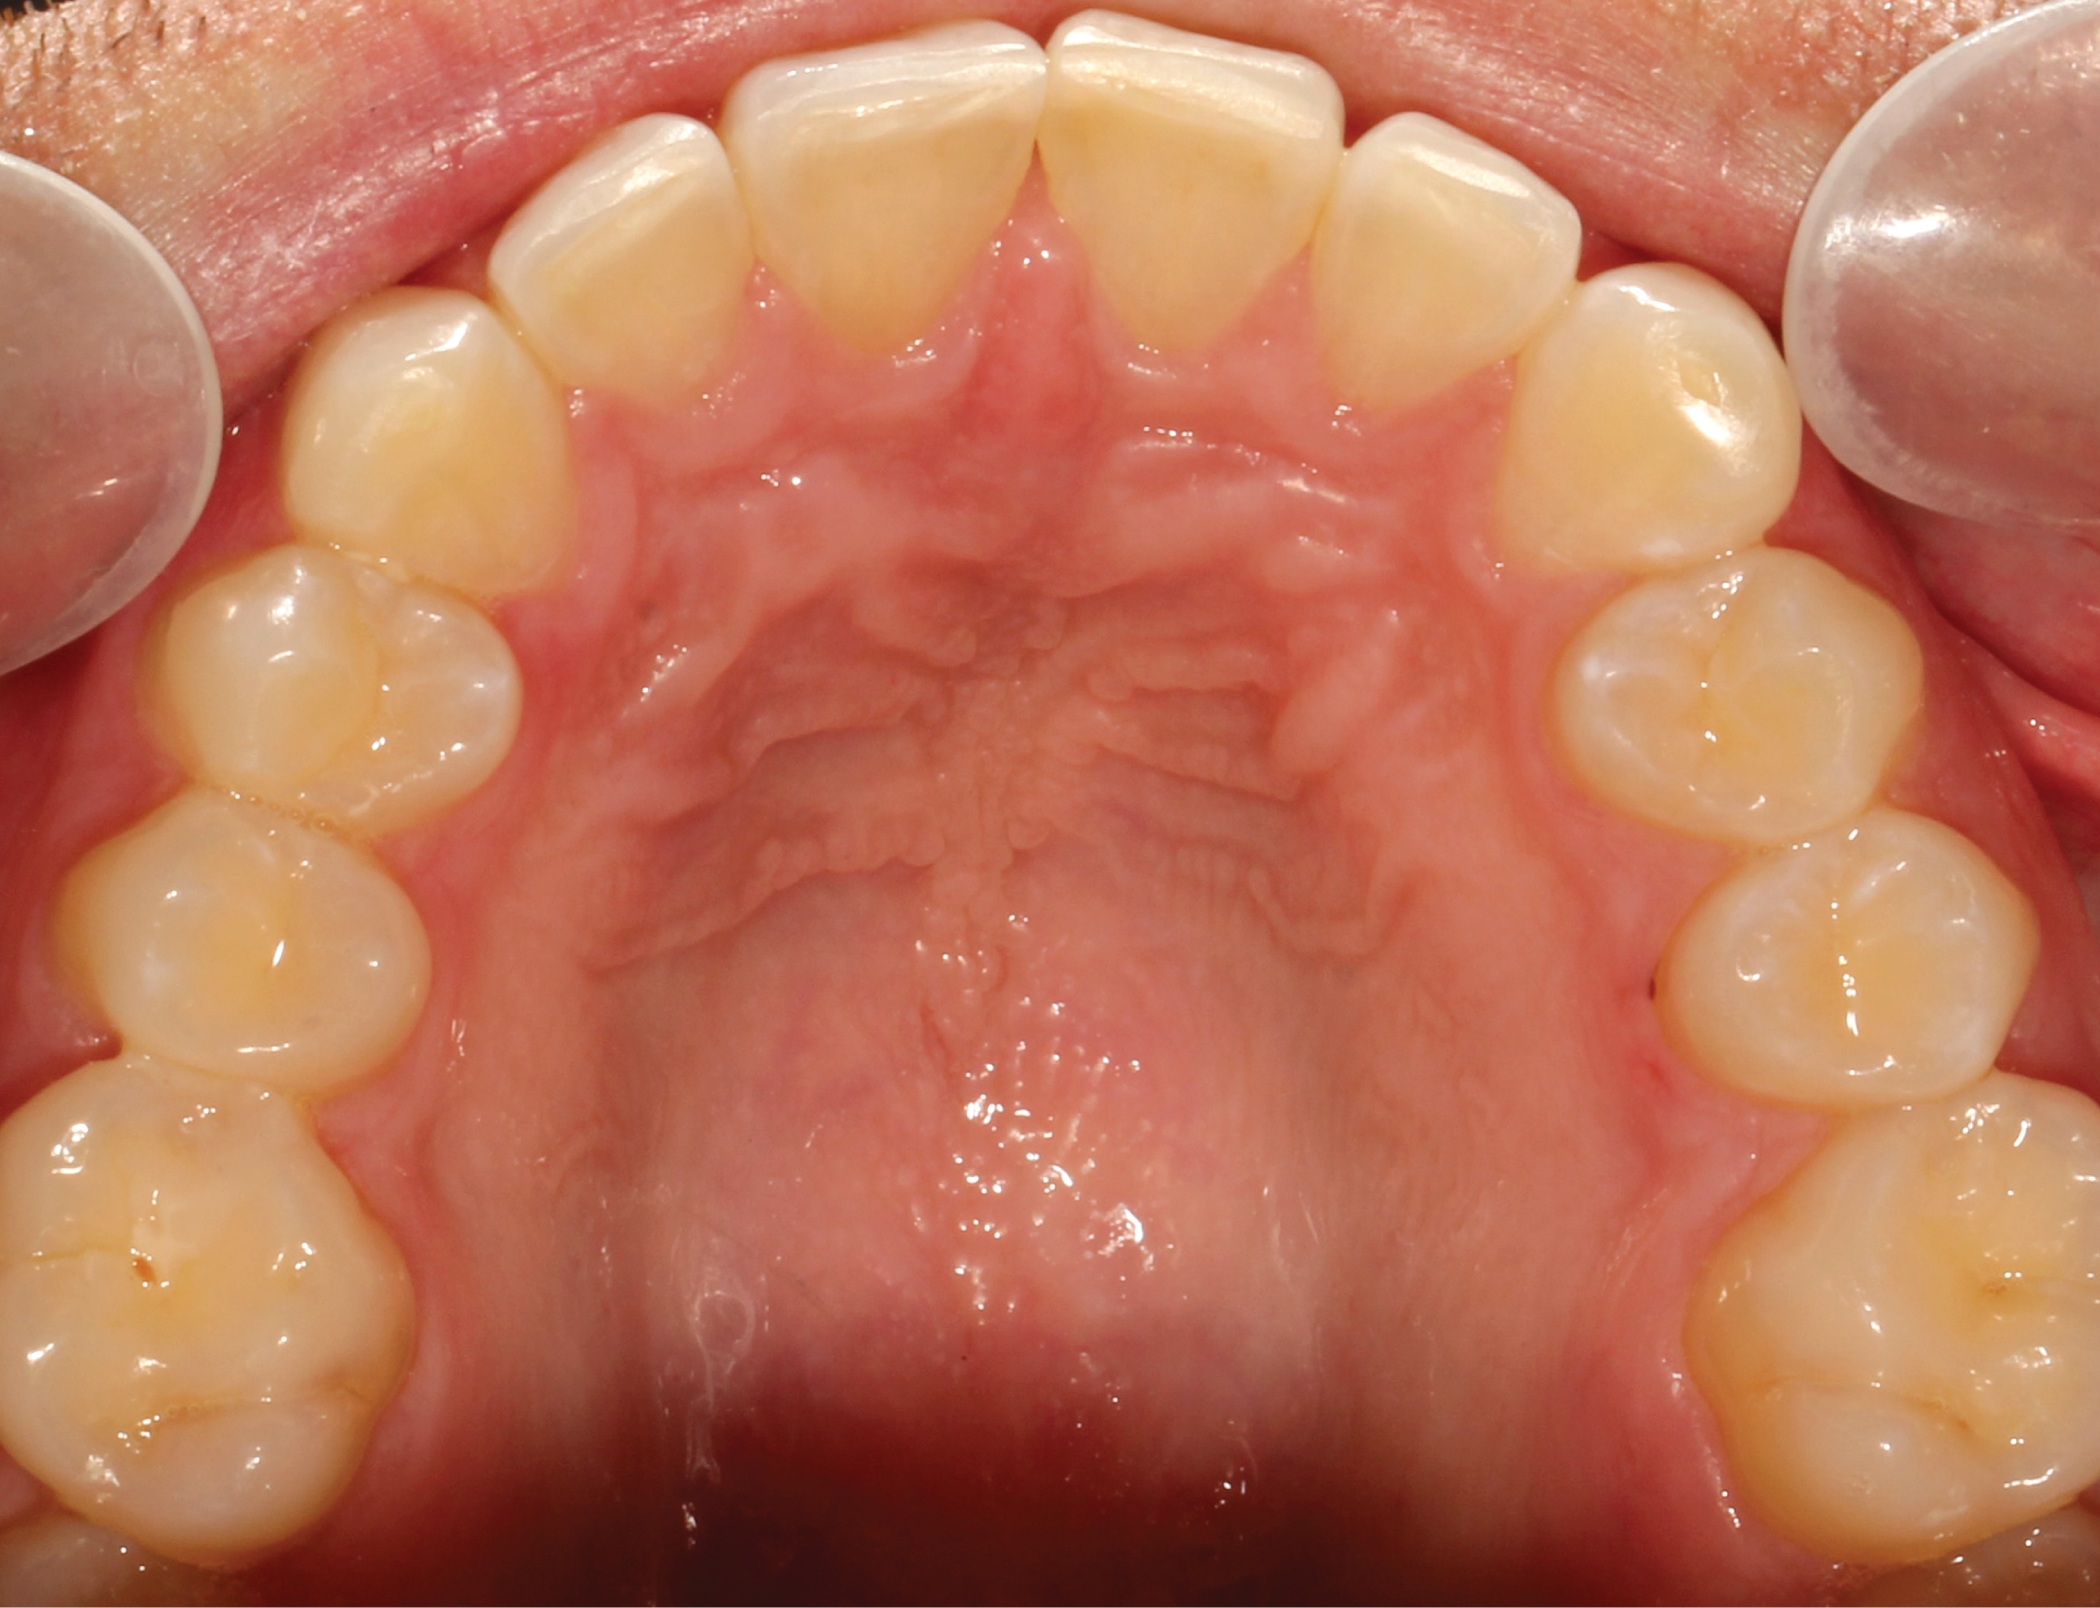

Fig. 5: Pre-op (upper occlusal view) Fig. 6: Pre-op (lower occlusal view)